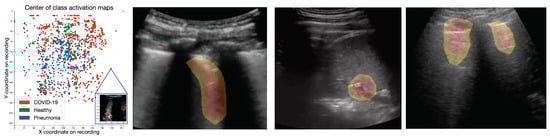

4.1. Class Activation Maps

4.1.1. Results

4.1.2. Expert Validation of CAMs for Human-in-the-Loop Settings